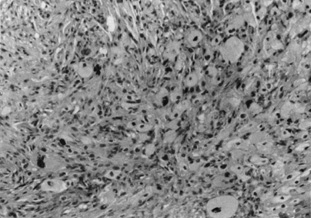

Erythema multiforme is a common pathway cutaneous reaction to drugs, viral or bacterial infections, or unknown causes. Characteristic “target“ lesions are seen as round-to-oval erythematous plaques with central darkening and marginal erythema. In its most severe form, Stevens-Johnson syndrome, the mucocutaneous surfaces (including the conjunctiva) are predominantly affected in association with a systemic syndrome, which may lead to death. Histologically, erythema multiforme and Stevens-Johnson syndrome are characterized by a dense lymphohistiocytic infiltrate that obscures the dermoepidermal junction associated with progressive necrosis of keratinocytes from the basilar to the uppermost portions of the epidermis. The intraepidermal and subepidermal vesiculation may lead to severe scarring of mucosal surfaces.